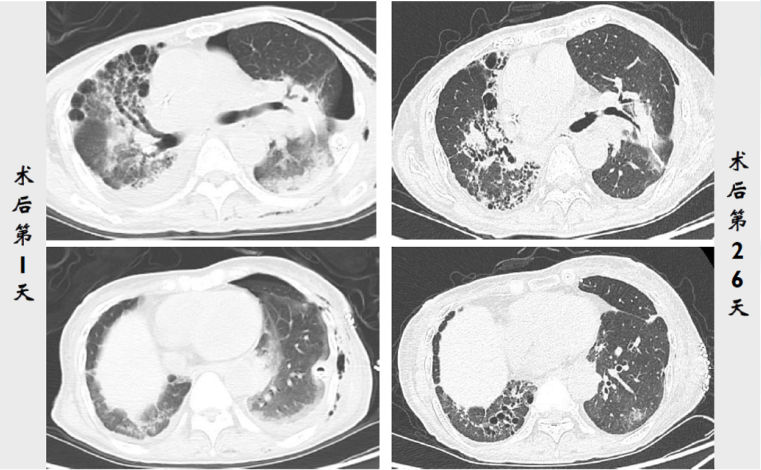

术后第1天:患者无发热,气管镜下示左肺下叶各基底段和背段管腔内少量黄白色黏痰;PCT 0.58 ng/ml(↑),血常规:WBC 12.9×109/L,NEUT% 81.3%,LYM 0.52×109/L。复查胸部CT:左侧移植肺肺野相对清晰,肺外带胸膜下可见少量斑片状磨玻璃(图9)

图片

9  患者左肺移植术后第1天胸部CT(2020-12-31)

再次复查胸部CT术后1天相比左侧移植肺肺野非常清晰无新发病变(图14)

14  复查胸部CT